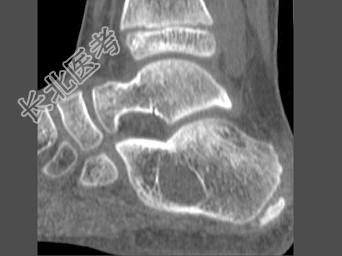

- 单项选择题女,15岁, 间歇性足跟痛,结合图像, 最可能的诊断是 ( )

A、骨囊肿

B、骨巨细胞瘤

C、骨髓瘤

D、骨纤维异常增殖症

E、动脉瘤样骨囊肿